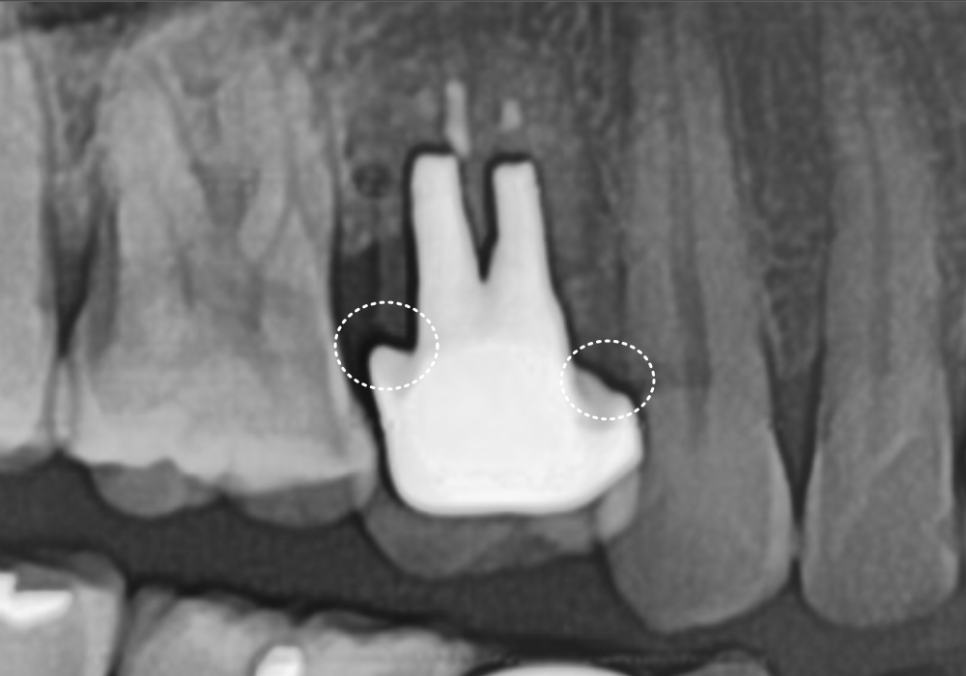

방사선 사진을 확인해 보니

예상보다 상태가 좋지 않았습니다.

신경치료 후 포스트(금속 기둥)까지

해둔 상태였고 뿌리 쪽으로

2차 충치가 상당히 진행되었습니다.

포스트까지 해두셨다는 건

크라운을 제작 당시,

치아 손상이 컸다는 것을 뜻하는데요.

250513

치아를 흔들어보니

안쪽이 많이 삭아,

약간의 흔들림까지 있었죠.

크라운을 제거하면 치아가 부러질

가능성이 높은 상태였기 때문에

재치료보다는 발치 후 임플란트가

더 안전하고 오래 쓰실 수 있는 방법이라고

환자분께 솔직하게 상태를 설명드렸습니다.